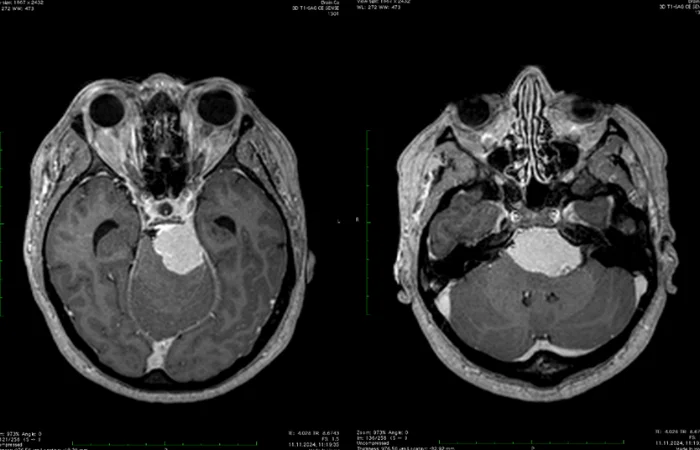

• магнітно-резонансну томографію (МРТ);

Ці обстеження допомагають визначити, чи залишилися залишкові клітини пухлини або з’явилося нове утворення.